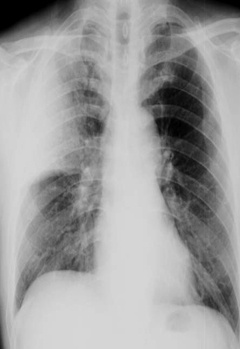

解题:片中可见肋膈角消失,根据公式得出胸腔积液